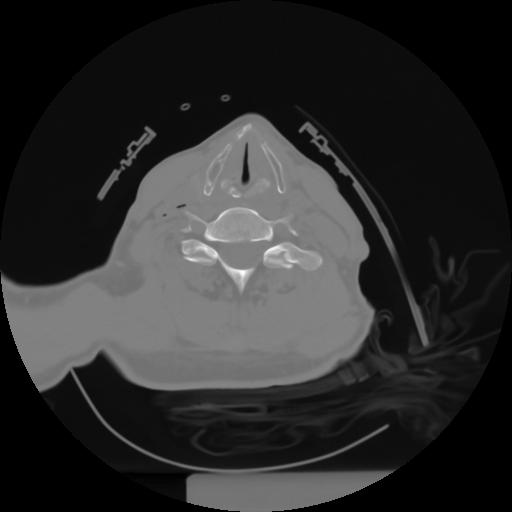

10 P.BLANDAS,,Axial,2.0,P.BLANDAS,,